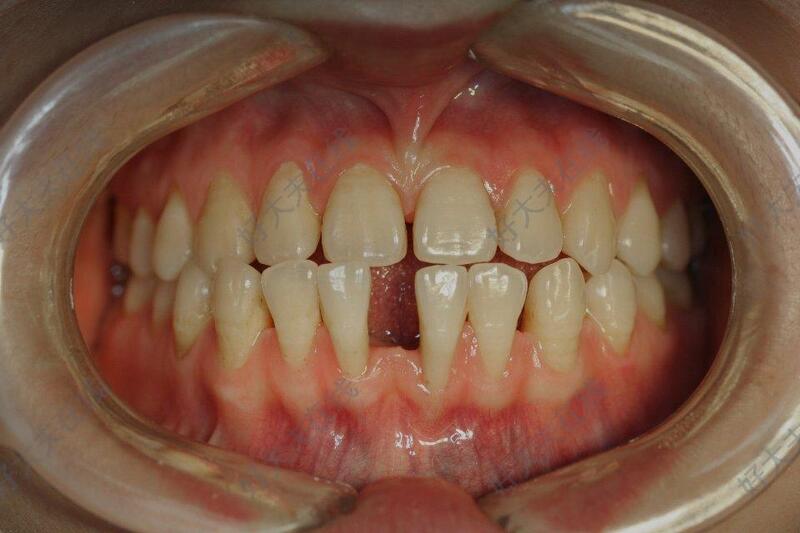

治疗后

- 治疗后365天

关闭散在间隙,建立良好咬合关系。美观改善,牙齿健康度提高,咬合功能改善